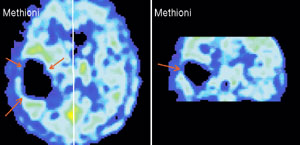

Именно наличие клиники во многом определяет возможности фундаментальных и прикладных исследований ИМЧ. Поэтому прежде всего несколько слов о ней. У нас прекрасные высококвалифицированные доктора и медсестры. Без этого нельзя: ведь мы на переднем крае, и нужна высочайшая квалификация, чтобы выполнять нерутинное, новое. У нас выполняются практически все стандартные манипуляции и наряду с ними и хирургическое лечение эпилепсии и паркинсонизма, проводятся психохирургические операции, в том числе и хирургическое лечение обусловленного героином обсессивно-компульсивного синдрома, знаменитая «пересадка мозга», точнее имплантация фетальной мозговой ткани, лечение магнитости-муляцией мозга, лечение афазии с помощью электростимуляции и многое другое. Накоплен десятилетний опыт клинических обследований с помощью позитронно-эмиссионной томографии. На рисунках приведена малая толика того, что может диагносцировать этот метод томографии. У нас лежат тяжелые больные, и мы стараемся помочь с помощью вышеперечисленных методов даже тогда, когда все остальные попытки были неудачны. Конечно, это удается не всегда. Но безграничных гарантий в лечении людей дать невозможно, а если кто-то дает их, это всегда вызывает очень серьезные сомнения.

Вообще, благодаря технике позитронно-эмиссионнной томографии (или сокращенно ПЭТ), стало возможно детальное изучение одновремено всех областей мозга, отвечающих за сложные “человеческие” функции мозга. Суть метода состоит в том, что малое количество изотопа вводят в вещество, участвующее в химических превращениях внутри клеток мозга, а затем наблюдают, как меняется распределение этого вещества в интересующей нас области мозга. Если к этой области усиливается приток глюкозы с радиоактивной меткой - значит, увеличился обмен веществ, что говорит об усиленной работе нервных клеток на этом участке мозга.

А теперь представьте, что человек выполняет какое-то сложное задание, требующее от него знания правил орфографии или логического мышления. При этом у него наиболее активно работают нервные клетки в области мозга, “ответственной” именно за эти навыки. Усиление работы нервных клеток можно зарегистрировать с помощью ПЭТ косвенно, по увеличению локального кровотока в активированной зоне. (Более ста лет назад было показано, что усиленная работа нервных клеток приводит к увеличению локального мозгового кровотока в этой области.)

Таким образом, удалось определить, какие области мозга “отвечают” за синтаксис, орфографию, смысл речи и за решение других задач. Мы предъявляем испытуемым различным образом организованные задания, при выполнении которых необходимо «задействовать» определенные свойства речи. Например, отдельные слова, предложения, связный текст. Сравнивая ПЭТ изображения, получаемые при этой деятельности, мы можем определить, где в мозге происходит обработка отдельного слова, где синтаксиса, а где смысла текста. Видны зоны, активирующиеся при предъявлении слов, неважно, надо ли было их читать или нет. Зоны, отвечающие за смысл текста, и другие. Интересно, и это будет рассмотрено ниже, что удалось обнаружить зоны, активирующиеся, чтобы «ничего не делать».

В настоящее время под руководством Н.П.Бехтеревой организованы исследования мозгового обеспечения творчества, то есть деятельности, результатом которой не являются механические или заранее запрограммированные действия с информацией, предъяв-ляемой в задании. Поясним на примере задания, похожего на то, которое нами реально использовалось в исследовании. Если испытуе-мому предъявить слова: “я, вечер, выходить, сад, дышать, свежий, воздух” и попросить составить из них рассказ, то его содержание очевидно. А если то же задание, но слова: “я, вечер, экзистециализм, электрон, утка, радар, балет, кабан?” Попробуйте связать их в историю. В настоящее время нельзя еще говорить о законченности этого исследования, но можно сказать, что удалось обнаружить корреляты творческой деятельности и в ЭЭГ, и в мозговом кровотоке, исследуе-мом с помощью ПЭТ. А ведь это значит, что удалось подсмотреть организацию, может быть, самой человеческой из известных деятельностей.